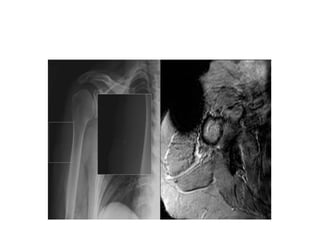

• #21 Fig. 15: This tiny piece of metal (square) visible on a shoulder x-ray caused the magnetic susceptibility artifact seen on the MR image (T2*). The loss of signal and image distortion caused by that metal piece significantly impairs our interpretation of the images.